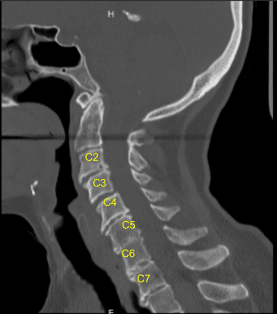

También comenzaron a desarrollar debilidad en el brazo y a aumentar el dolor. El examen físico mostró debilidad en los músculos de la mano. La resonancia magnética (RM) de la columna cervical mostró un extenso foraminal neural y estenosis del canal central.

La tomografía computarizada sugirió enfermedad degenerativa del disco en múltiples niveles. El paciente dio su consentimiento informado, entendiendo todos los riesgos, beneficios y alternativas a la cirugía. Discutimos las opciones de tratamiento y acordamos seguir adelante con la discectomía cervical anterior y la fusión C3 a C6.